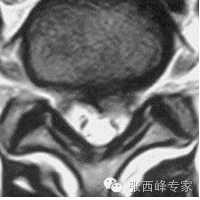

水平位腰5骶1椎间盘突出